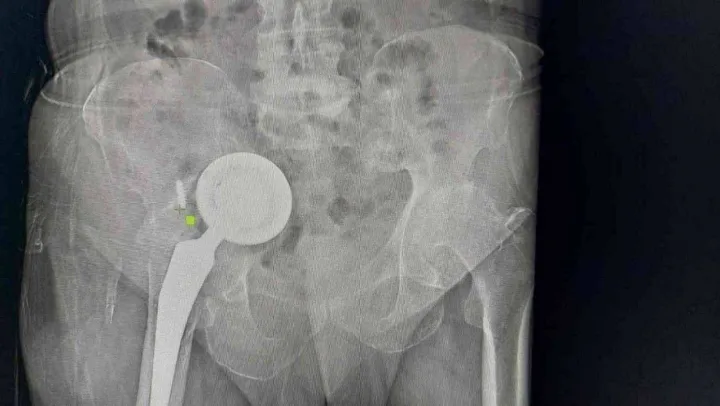

Adıyaman'da yaşayan 74 yaşındaki Ömer Demir, geçtiğimiz yıllarda kalça bölgesinde hissettiği rahatsızlıklar sonrası doktora gitti. Kalçasında kireçlenme olduğu belirlenen Demir, kalça protezi ameliyatıyla şikayetlerinden kurtuldu. Edinilen bilgiye göre zaman içerisinde yeniden ağrılar hissederek hastaneye başvuran Demir'in protezine revizyon ameliyatı yapıldı. Ancak bir süre sonra yaşlı adamın ağrıları yeniden kendini gösterdi ve uzmanlar operasyon gerekliliğini ifade etti. İddiaya göre geçirdiği operasyonlar sonrası tekrar ameliyat olmak istemeyen Demir, gittiği birçok doktoru dinlemedi, protezi ise karın içi ve uyluk kemiğinde ilerlemeye başladı. Zamanla ağrıları dayanılmaz hale gelen yaşlı adam, en son Başakşehir Çam ve Sakura Şehir Hastanesi'ne geldi. Burada yapılan tetkikler sonrası protezin diğer organlarını olumsuz etkileyecek şekilde vücudunda ilerlediğini duyan yaşlı adam, ameliyata onay verince acil şekilde operasyona alındı. Başakşehir Çam ve Sakura Şehir Hastanesi Ortopedi ve Travmatoloji Uzmanları Dr. Mustafa Özçamdallı ve Dr. Necati Doğan'ın ekipleriyle gerçekleştirdiği operasyonla protezin üst kısmı karın içinden alt kısmı ise hastanın bacağından çıkarıldı. Yeni protez ise başarılı bir şekilde bölgeye yerleştirildi. Hastada yaşanan durumla çok sık karşılaşmadıklarını ifade eden Uzm. Dr. Özçamdallı ve Doğan tedaviye ilişkin bilgi verirken Demir, yaşadıklarını anlattı.

Demir'in geldiği pozisyonu ve uyguladıkları tedaviyi anlatan Dr. Necati Doğan, 'Hastamıza yıllar önce kalça kireçlenmesi nedeniyle kalça protezi uygulanmış, bu protez uygulamalarında sıklıkla başarılı sonuçlar elde ederiz. Daha önce gittiği hastanelerde bu protezin yenilenmesi gerektiğini hastamıza söylemişler. Hastamız o anki risklerden dolayı bu süreci kabul etmemiş, ötelemiş ve yaklaşık 2-3 yıl boyunca bu protezi kullanmaya devam etmiş. Protezde ilerlemeye devam etmiş. Bize başvurduğunda artık protez karın içindeki organların arasına kadar yerleşmişti. Bacakta ciddi şişlikleri, hareket kısıtlılıkları oluşmuş, yürüyemez hale gelmişti. Yenileme ameliyatı gerektiğini söyledik ve hastamız artık mevcut tablosundan ileri derecede şikayetçi olduğu için belirli riskleri, ameliyatı kabul etti. Protezin bu kadar ileriye gitme aşaması sık karşılaştığımız bir şey değil, daha erken evrelerde geldiklerinde sadece kalça bölgesi açılır. Daha uyumlu protezlerle kalçadaki implant değiştirilir ve hayatına geri döner. Ama bu hastamız artık normal bölgeden çıkarılamayacak derecede ilerlemiş formuyla geldiği için bizim bu protezi kalça bölgesinden çıkarıp onarmamız imkansızdı. İlk olarak karın içindeki kısımları çıkartmak için karın bölgesinden girdik. Protezin yuva baş dediğimiz kısımlarını karın içinde mesanenin, bağırsakların, damar sinir paketlerinin arasından güvenli ve sorunsuz bir şekilde çıkarttık. Daha sonra bu kemikte oluşmuş ileri derecedeki defekti de onarmak gerekiyordu, buraya da uygun platinlerle tekrardan yeni yapılan protezler içeri gelmesin diye yeni platinlerle bir destek kısmı oluşturduk. Karın iç kısmındaki işimiz bitti daha sonra ikinci bir aşamada kalça bölgesinde kalan kısmı çıkarttık. Şu anki protezimiz gayet stabil ve hemen hareket etmeye, yük vermeye, yürümeye uygun bir protez. Vatandaşların protezlerini düzenli takip ettirmeleri gelişen herhangi bir yeni şiddetli ağrı ve problemlerde mutlaka en erken dönemde bu aşamalara gelmeden kontrollerini yaptırmalarını öneririm' dedi.

Protezin üst kısmının karın içinden alt kısmının ise bacaktan çıkarıldığını ifade eden Ortopedi ve Travmatoloji Uzmanı Dr. Mustafa Özçamdallı, 'Hastamız bize geldiğinde yürüyemez bir vaziyetteydi daha önce birkaç kez operasyon geçirmiş ve protezi karın dediğimiz boşluğa kadar ulaşmış durumdaydı. Hastanın damarlarında ve sinirlerinde hasarlar meydana getirebilecek seviyedeydi. Özel dizayn edilmiş kafes dediğimiz protezlerle ve daha uzun revizyon dediğimiz protezlerle hastamızın operasyonunu başarılı şekilde gerçekleştirdik. Böyle durumlar hastaların ilerleyen dönemlerinde dolaşımını bozup bacaklarımı kaybetmeye kadar gidebilir. Bu hastamızda ek birtakım rahatsızlıklar olması sebebiyle diyabet, kalp rahatsızlığı, sebebiyle yatağa bağımlı olması bu hastalarda mortalite dediğimiz durumu arttırmaktadır. Bu çok sık karşılaştığımız bir hasta grubu değil. Kesinlikle kalça protezi yapılan hastalarımızın kontrollerine rutin olarak gitmeleri gerekir. Bu hastamız biraz operasyonlardan çekinmiş ve birkaç operasyona girince, çok yüksek olduğu anlatılınca korkmuş ve dolayısıyla bu şekilde hayatını bir 3-4 yıl daha idame ettirince protezin daha da aşınıp leğen kemiğinin yukarısına doğru çıkmasına sebep olmuş. Kendisine ameliyat önerilmesine rağmen ameliyatlarını kabul etmemişti ve bu protez leğen kemiğinde aşınmaya sebep olup karın içi organlara kadar ilerlemiş vaziyetteydi. Biz protezi 2 parça halinde çıkarttık. Protezin üst kısmını karın bölgesinden, alt kısmını uyluk kemiğinden çıkarttık' diye konuştu.